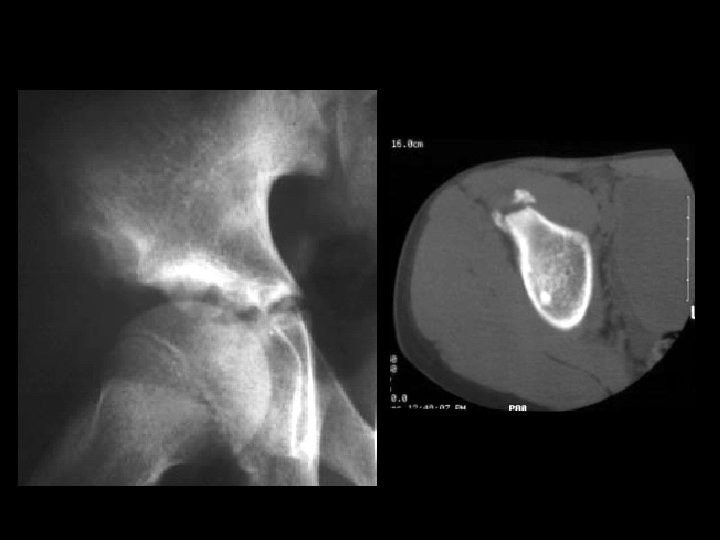

Hemangioma • Findings: – expansile lesion of the proximal tibia containing fine bony septations and a large course calcification – CT scan shows a lacey appearance • ddx: – Paget’s dz – ABC